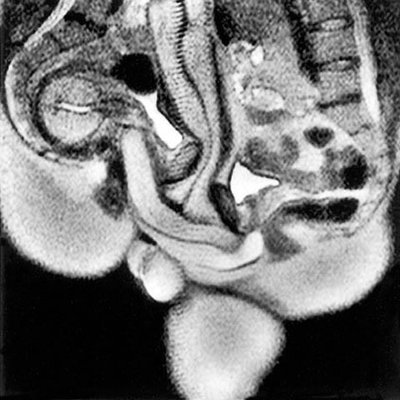

Doi dintre colegii de echipă ai doctorului Pek Van Andel (Ida Sabelis şi Eduard Mooyaart) s-au oferit voluntari să facă sex în tubul RMN.

Aproape un ilustru necunoscut, Van Andel a cerut unui tehnician RMN să adune toate imaginile statice şi să le asambleze într-un film.

Concluzia studiului: Este posibilă obţinerea de imagini RMN ale organelor sexuale feminine şi masculine în timpul actului sexual, iar aceste imagini contribuie la înţelegerea anatomiei acestora.